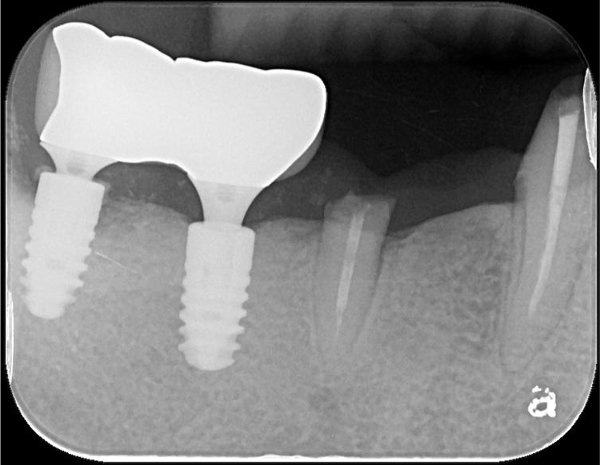

術後X光

顯微根管治療:#43